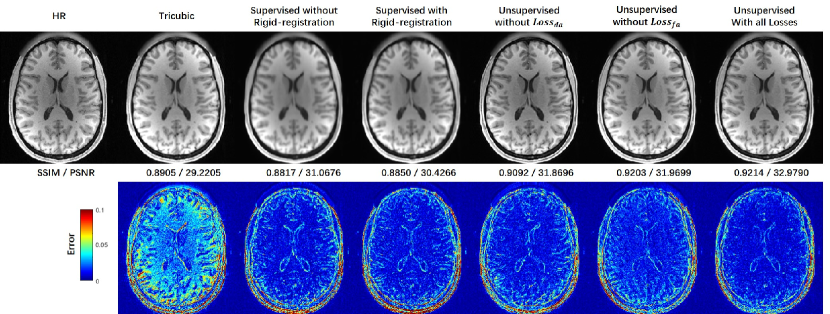

We evaluated our network in various configurations on the same task of SRR for misaligned LR and HR datasets to find the best performance. The effect of DA in the image space and latent feature space was evaluated. Besides, we compared our network to the same backbone network trained in the supervised strategy with the misaligned training data to reveal the effect of the degradation-learning modules. As shown in Table 1, all the configurations of the UDEAN outperformed the supervised learning using the same generator by over 0.014/0.74 dB in SSIM/PSNR using misaligned LR and HR image from the HCP dataset with the scale factor of . Among the configurations of the UDEAN, the performance was downgraded by 0.009/0.75 dB or 0.002/0.71 dB in SSIM/PSNR when DA in only latent feature space or image space was applied, respectively.

Furthermore, Fig. 5 shows the visual effect of the reconstructed SR images and the error maps to the HR images. The SR image reconstructed by the supervised methods were highly blurry either with or without rigid image registration. On the contrary, the quality of SR images reconstructed by the UDEAN was significantly improved even with DA only in latent feature space or image space. The errors of the reconstructed anatomical structures were further reduced when DA in both domains was applied in the training process.